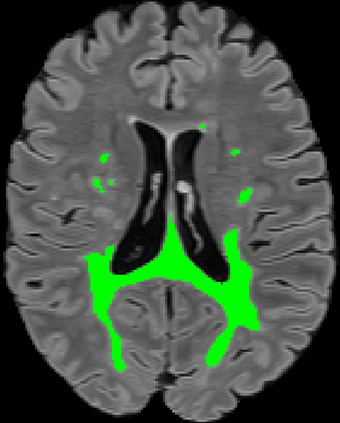

Recently, segmentation methods based on Convolutional Neural Networks (CNNs) showed promising performance in automatic Multiple Sclerosis (MS) lesions segmentation. These techniques have even outperformed human experts in controlled evaluation conditions such as Longitudinal MS Lesion Segmentation Challenge (ISBI Challenge). However state-of-the-art approaches trained to perform well on highly-controlled datasets fail to generalize on clinical data from unseen datasets. Instead of proposing another improvement of the segmentation accuracy, we propose a novel method robust to domain shift and performing well on unseen datasets, called DeepLesionBrain (DLB). This generalization property results from three main contributions. First, DLB is based on a large group of compact 3D CNNs. This spatially distributed strategy ensures a robust prediction despite the risk of generalization failure of some individual networks. Second, DLB includes a new image quality data augmentation to reduce dependency to training data specificity (e.g., acquisition protocol). Finally, to learn a more generalizable representation of MS lesions, we propose a hierarchical specialization learning (HSL). HSL is performed by pre-training a generic network over the whole brain, before using its weights as initialization to locally specialized networks. By this end, DLB learns both generic features extracted at global image level and specific features extracted at local image level. DLB generalization was validated in cross-dataset experiments on MSSEG'16, ISBI challenge, and in-house datasets. During experiments, DLB showed higher segmentation accuracy, better segmentation consistency and greater generalization performance compared to state-of-the-art methods. Therefore, DLB offers a robust framework well-suited for clinical practice.